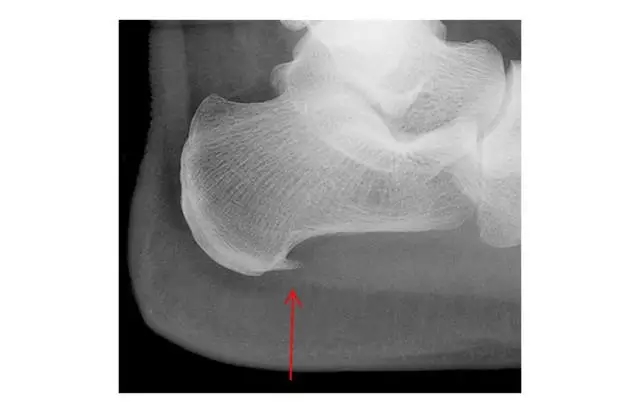

三、被冤枉的足跟骨刺如下图(红色箭头所指),跟骨骨刺看着就让人觉着疼,所以“骨刺”在大家心目中被妖魔化成了足跟痛的罪魁祸首。但其实,足跟骨刺并不是导致脚底跟疼痛的原因,研究表明,有足跟骨刺的人群中,63%的人是没有任何的疼痛症状。

足跟骨刺是跟骨骨质的增生,跖筋膜活动过多,过度收缩变得紧张造成跖筋膜有细微的撕裂和发炎变得不舒服,造成了跖底筋膜炎这时人体的自我保护机制形成骨刺,想要保护过度收缩的而受伤的跖筋膜。